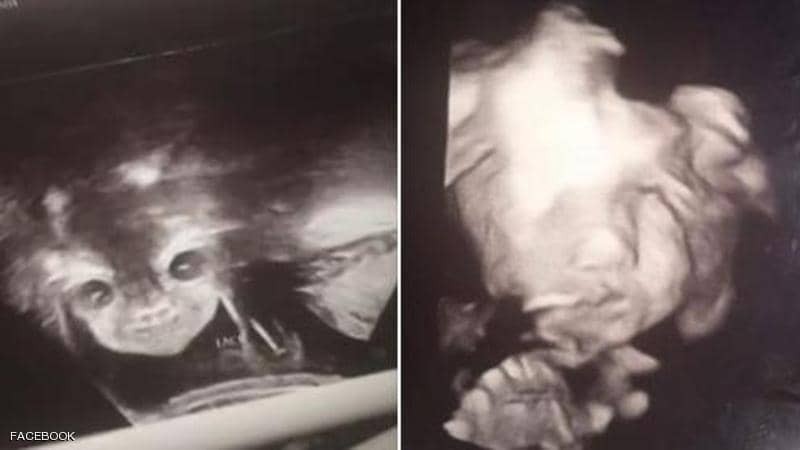

فوجئ أبوان بصورة بدت مخيفة لطفلهما المنتظر وهو في بطن أمه، خلال جلسة في معمل الموجات فوق الصوتية للاطمئنان على حالته.

وأثارت صورة "الجنين الشيطان" حسب تعبير الأم، التي انتشرت بشكل واسع على مواقع التواصل الاجتماعي، ضجة كبيرة حول العالم، فضلاً عن قلق والديه.

ونشرت الأم المراهقة التي تدعى إيانا ألستون (17 عاما)، الصورتين اللتان التقطتا لجنينها، على حسابها في "فيسبوك"، وعلقت عليها بالقول: "معظم الأطفال يختبئون من الكاميرا. انظروا إلى طفلتي الشيطانية".

وأضافت: "كانت تبدو عادية، لكن عندما علمنا أننا سنرزق بفتاة، وتم وضع الجهاز على بطني مرة أخرى، فتحت عينيها وابتسمت. أحب هذه الطفلة الشيطانية جدا".